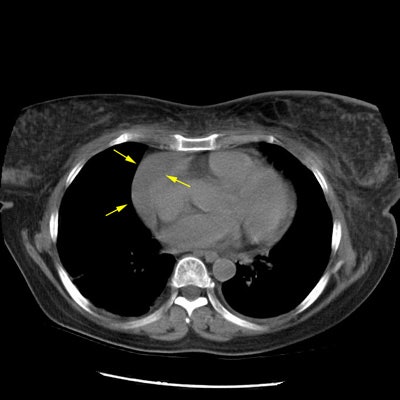

Earlier interstitial lung disease:

The case below is an example of interstitial lung disease at an earlier stage in a patient with a history of breast cancer (and a prior right mastectomy). There are patchy areas of fine subpleural "lace-like" intralobular interstitial thickening. Thickened interlobular septa are also seen, as is honeycombing- particularly in the posterior costophrenic sulci. The fibrosis associated with interstitial lung disease produces architectural distortion which is not seen in patients with lymphangetic metastases.